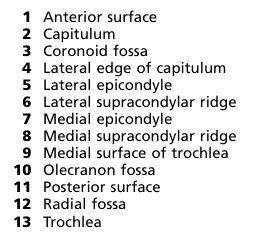

Identify medial condyle?

Structure 7

Nerve related to medial condyle?

Ulnar nerveNerve injury (sensory and motor)?

Motor

• Claw hand with ulnar paradox (ulnar paradox).Sensory

• Loss of sensation of the medial ½ of the palmar and dorsal aspects of hand and fingers. -